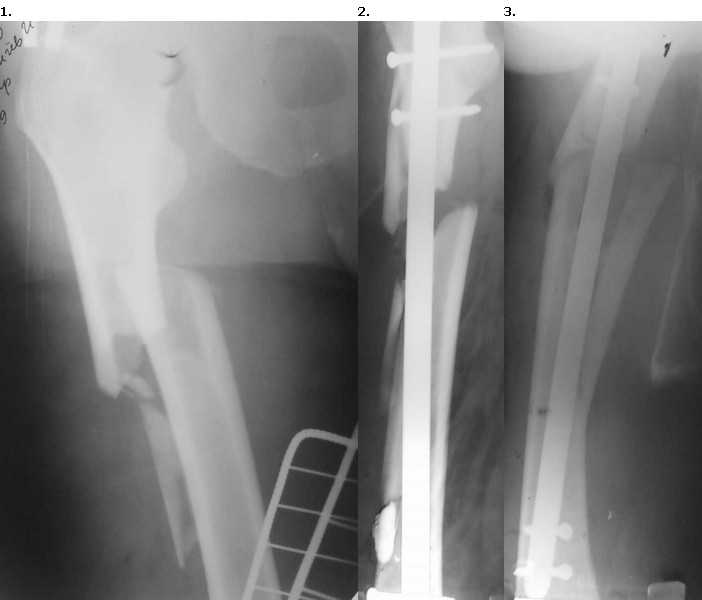

Доброго времени суток, уважаемые коллеги. Пациент 56 лет поступил в отделение 28.12.09 со свежим переломом в/3 правого бедра. 15.01.10 произведен закрытый БИОС гвоздем Sanatmetal.

(d13мм), во время которого произошло раскалывание проксимального и дистального отломков. ЭОПа в больнице нет, для определения локализации направителя пользовались стареньким "Арманом". После заведения гвоздя по проводнику снимки на столе больше не делали, дистальное блокирование оч.быстро с использованием электромагнитной навигации. В послеоперационном периоде выраженные боли и отек. На контрольных рентгенограммах вот такая картина.

После посмотрели за экраном - гвоздь стоит стабильно как в проксимальном, так и в дистальном отломке,но контакта между проксимальным и дистальным нет. Вопросы: